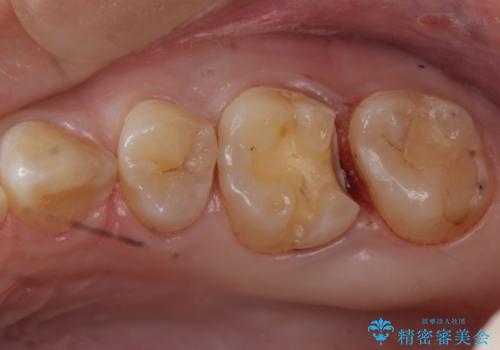

歯と歯の間に隠れた虫歯 セラミックインレーによる治療

写真ではなかなか分かりづらいですが、歯と歯の間に虫歯があることがレントゲン画像から読み取ることができます。